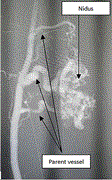

Preoperative embolization of high-flow peripheral AVMs using plug and push technique with low-density NBCA/Lipiodol

Anh Binh Ho and others

Journal of Surgical Case Reports, Volume 2020, Issue 9, September 2020, rjaa316, https://doi.org/10.1093/jscr/rjaa316